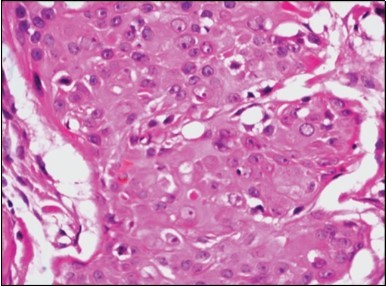

Granular arrangement of malignant cells and intercellular bridges are conspicuous with the demonstration of nuclear atypia, pleomorphism, prominent mitosis and tumour necrosis. A peripheral palisade is discernible within the cellular aggregates. Mitotic figures are common and can be quantified as up to 12 mitosis/ high power field. Tumour differentiation can prominently be of the ductal category with the demonstration of intra-cytoplasmic lumina. Comedo type tumour necrosis is evident along with foci of squamous differentiation The neoplasm is reactive to periodic acid Schiff ‘s (PAS) stain. (Figure 1, Figure 2, Figure 3, Figure 4, Figure 5, Figure 6, Figure 7, Figure 8, Figure 9, Figure 10, Figure 11, Figure 12, Figure 13.

Figure 4.Cellular atypia, mitosis and focal necrosis in eccrine porocarcinoma(16).